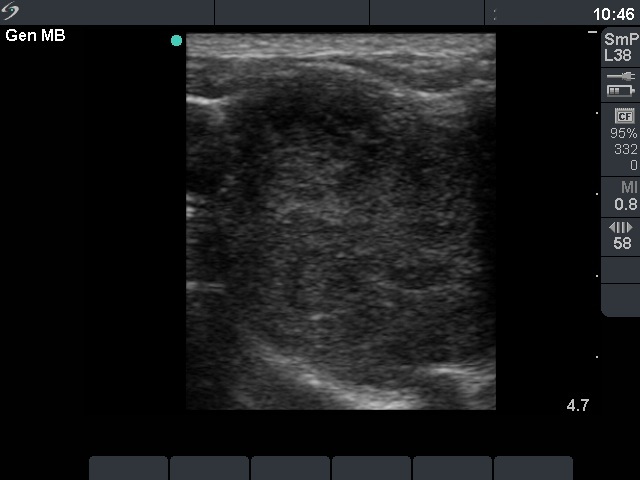

Ultrasonography. There was a large hypoechogenic nodule with irregular borders in the right thyroid. The vascularization was decreased.